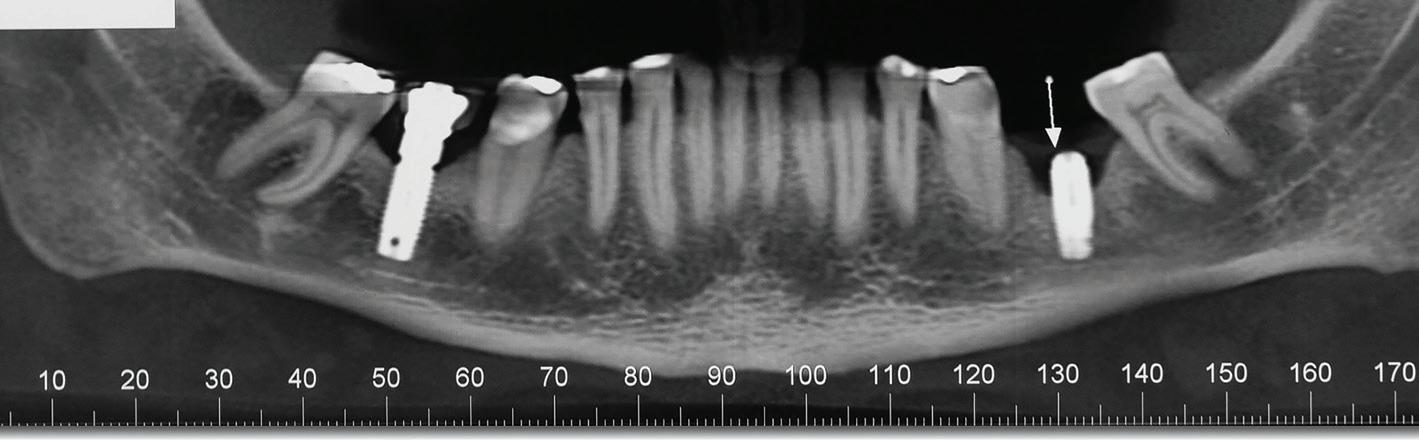

Chu44 35 M Swelling on left side of cheek FP,

Ferreira et al45 19 F Moderate headache, nausea, vomiting, left facial hypesthesia, low visual acuity FP, PP

Sohal et al46 24 M Massive swelling in right side of face FP

Linaburg et al47 50 F Massive swelling in left side of face Acanthomatous, FP

Abbreviations: F, female; FP, follicular pattern; M, male; NR, not reported; PP, plexiform pattern.